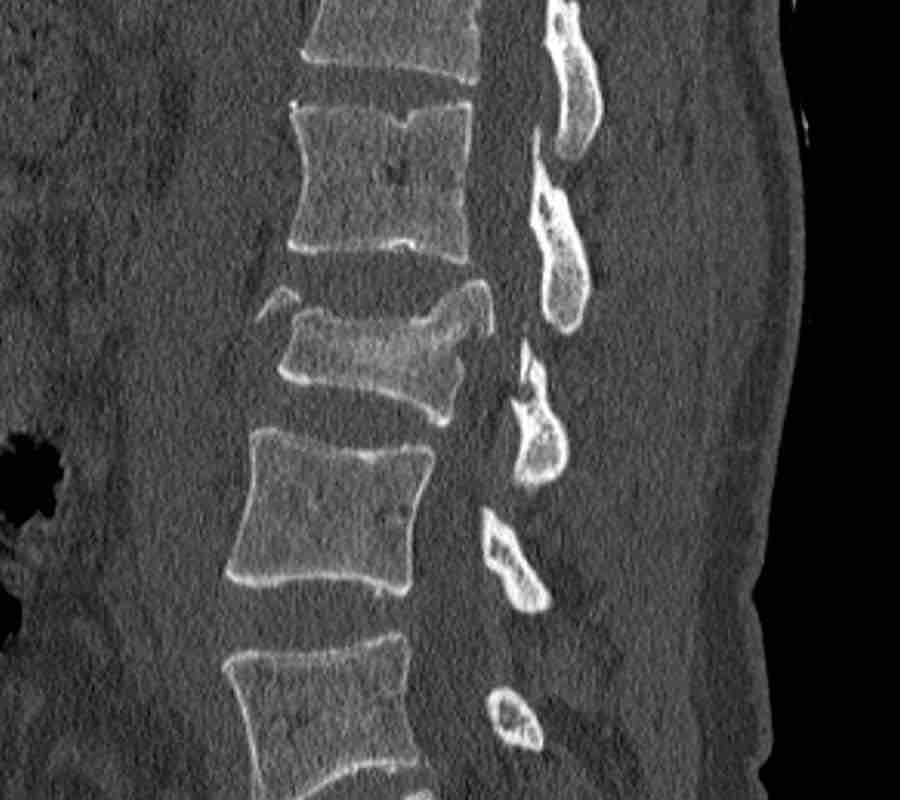

What is the highest AO-type of injury?

Findings:

- No C or B injury

- Fracture of the vertebral body with involvement of both endplates (1+1 points), no posterior wall involvement

Conclusion

injury type A2